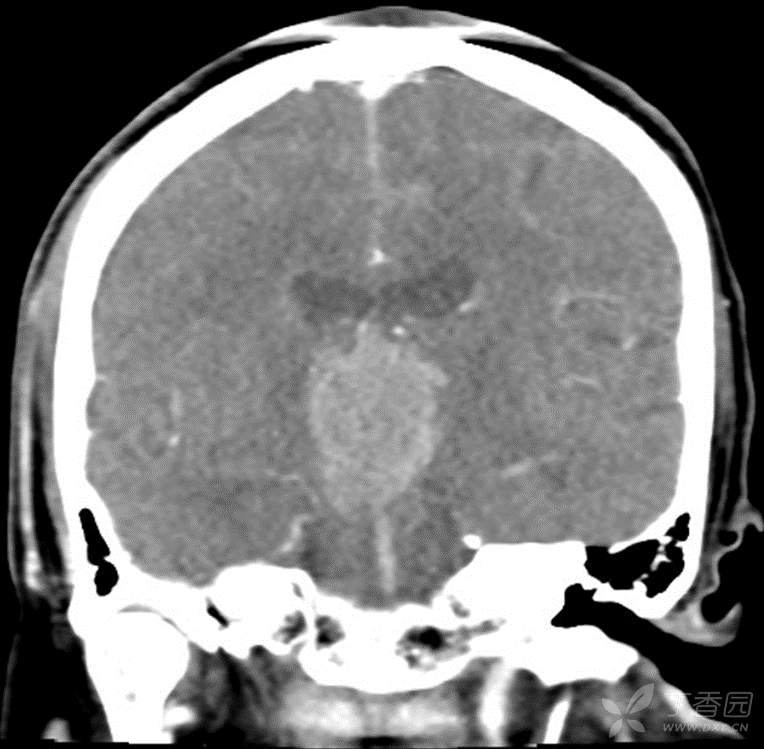

男,44岁,记忆力下降、乏力5月余,多尿3月余,CTMR全,疑难病例,能正确诊断吗?

图像不多,能诊断正确吗?有特征性吗?

增强